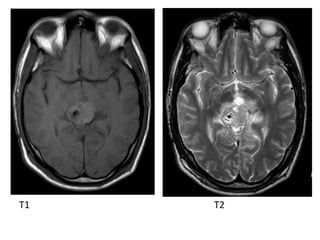

b) MRI

-T1 : isointense or slightly hyperintense to adjacent

brain

-T2 : isointense or slightly hyperintense to adjacent

brain, may have areas of cyst formation, central

calcification appears low signal (engulfed pineal

gland)

-T1+C : vivid and homogeneous

T1

T1+C

T1 T2